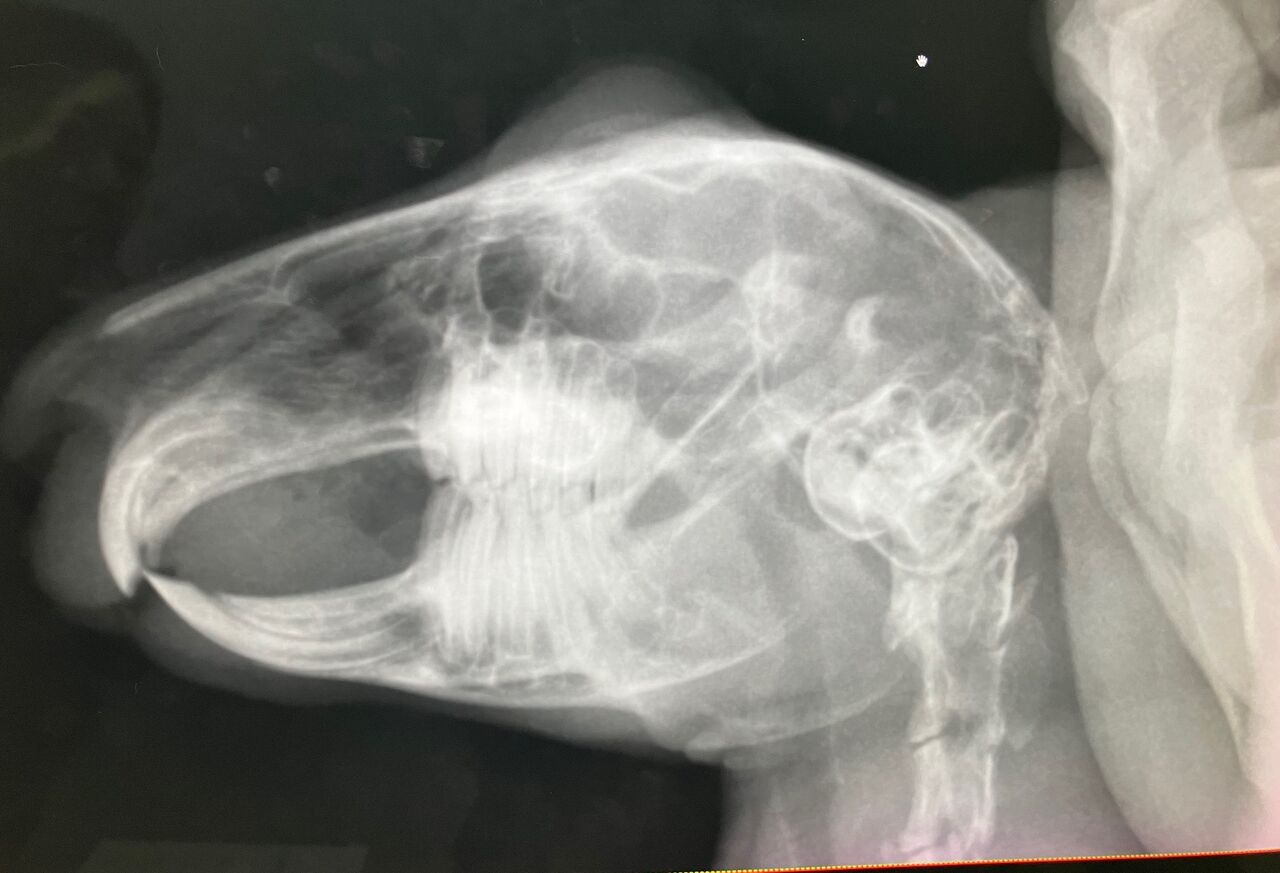

口内検査で歯、奥歯右下3番目が少し内側に向いてたのでカット処置。